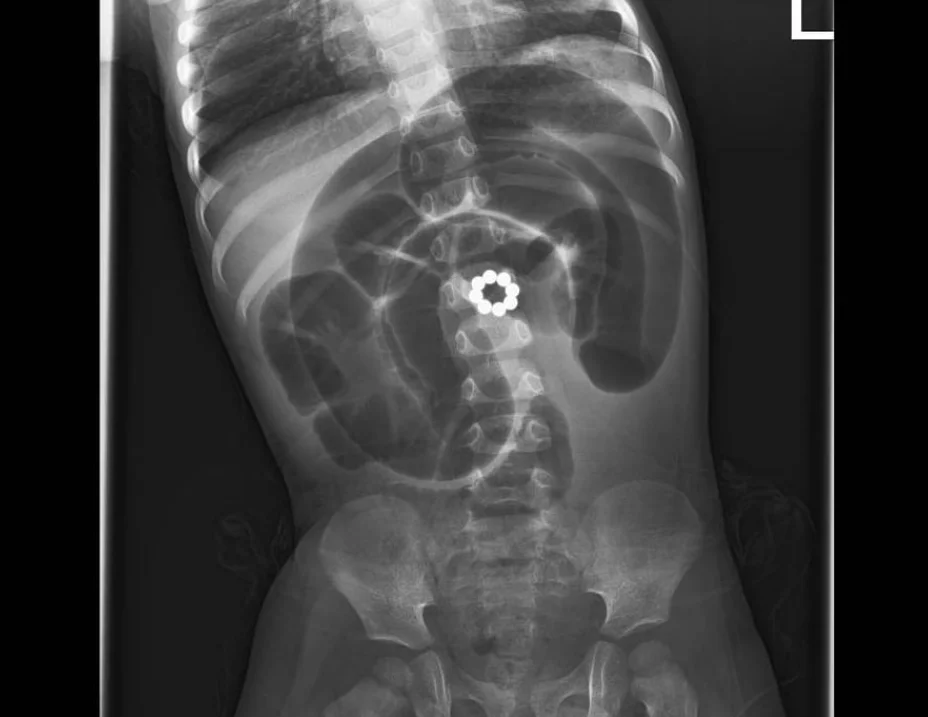

עד הוסיף האב כי "לאחר בדיקות מקיפות שכללו צילום חזה ובטן ואולטרסאונד גילו שהבן שלי בלע 8 מגנטים קטנים שגרמו לנזק רב במעיים. תוך שעה מרגע האבחון הוא כבר נכנס לניתוח חירום שהציל את חייו. הצוות שטיפל בנו עשה הכל ברגישות ומקצועיות, הם תמכו בנו ברגעים הקשים".

ד"ר מרק ארקוביץ', מנהל המחלקה לכירורגית ילדים, שביצע את הניתוח בפעוט, הדגיש את המסוכנות והסביר: "מגנטים הם משחק מסוכן מאוד עבור ילדים. כאשר הפעוט בולע יותר ממגנט אחד, הם נצמדים זה לזה בתוך מערכת העיכול ועלולים לגרום לקרעים במעיים ואז תכולת המזון במעיים נפלטת אל הבטן וזו סכנת חיים של ממש. במקרה הזה המטופל הגיע עם נמק במעי אחרי ששמונת המגנטים שהוא בלע נצמדו אחד לשני וחסמו את זרימת הדם לאזור. המגנטים חסמו את תנועת המזון במערכת העיכול."

לדבריו, "בניתוח החירום הוצאנו את המגנטים, והסרנו שני אזורים שהיו נמקים וביצענו השקה של החלקים הבריאים. לצערי, פעוטות שבולעים מגנטים זה אירוע שכיח והטיפול הכי טוב הוא פשוט למנוע מקרים אלו. הרחיקו מהישג ידם של ילדים מגנטים ואם עולה חשש שהפעוט בלע מגנטים, או חפצים אחרים חשוב מייד לפנות לטיפול רפואי".